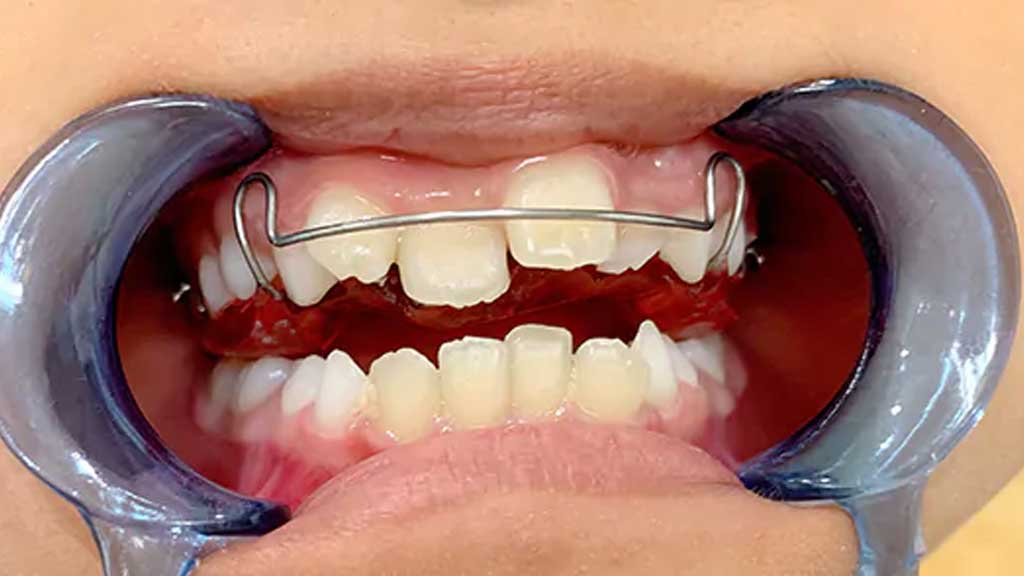

ارتودنسی ثابت موضعی

در این روش، براکت فقط روی همان دندان (و گاهی ۲ دندان کناری) نصب میشود.

ارتودنسی تک دندان جلو

ارتودنسی تک دندان جلو، به این معنا نیست که فقط روی همان یک دندان سیم بسته میشود. معمولاً برای ایجاد تکیهگاه و اهرم فشار، براکتها روی ۴ تا ۶ دندان جلو نصب میشوند تا آن یک دندان کج به جای خود بازگردد. بهترین روشها برای این درمان عبارتند از:

- ارتودنسی ثابت جزئی (Limited Braces)